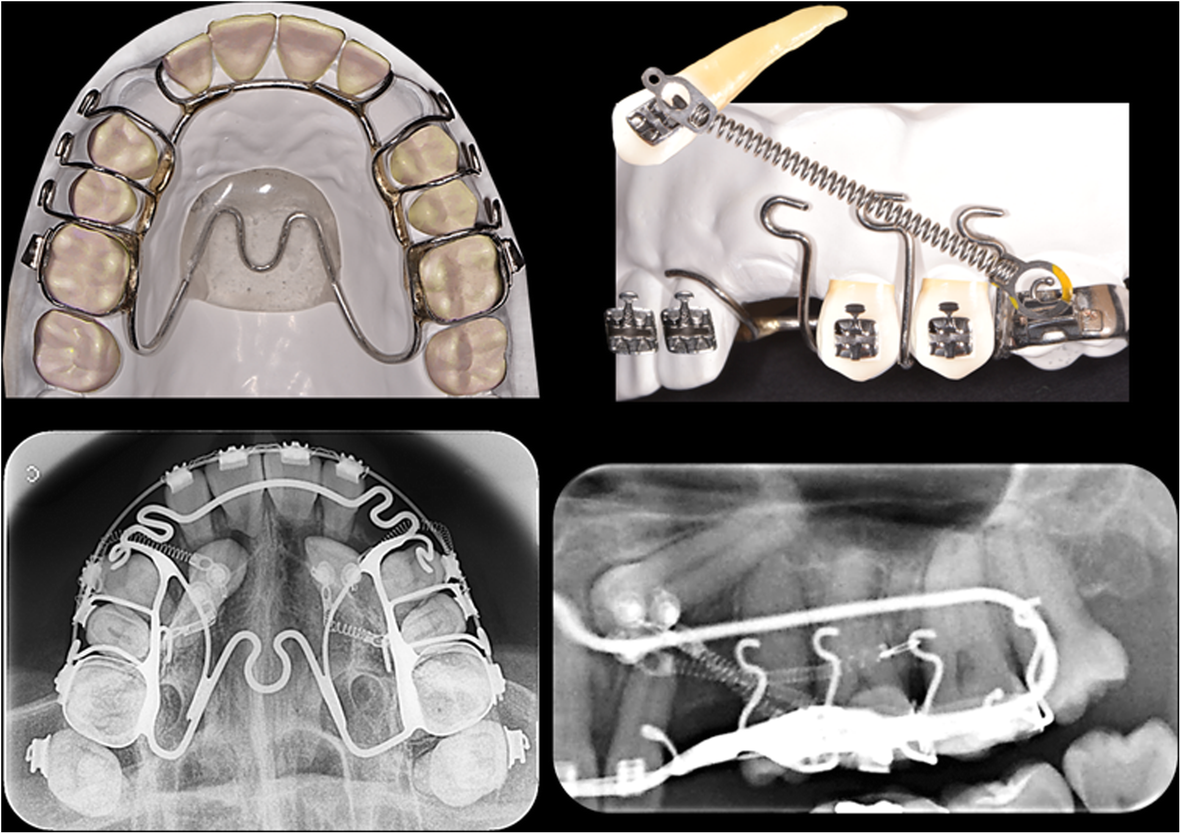

Figure 18 from Orthodontic traction of impacted maxillary canines using Orthodontic Traction Thus, this work aims to show,. Transalveolar autotransplantation (9 canines) and orthodontic traction (8 canines) were the most frequently chosen treatment methods. Orthodontic brackets are placed before the surgical exposure. Surgical techniques along with orthodontic treatment are widely used for correct positioning in the arcade. It illustrates the topic by presenting a treatment delivered to a 13 year 7 months. Orthodontic Traction.

ab Radiographic monitoring showing the orthodontic traction process Orthodontic Traction Teeth are required to be aligned and leveled because orthodontic. A ramus miniscrew is an effective and viable treatment option for the orthodontic traction of deeply impacted mandibular molars. Transalveolar autotransplantation (9 canines) and orthodontic traction (8 canines) were the most frequently chosen treatment methods. Surgical techniques along with orthodontic treatment are widely used for correct positioning in the arcade.. Orthodontic Traction.

Threedimensional evaluation of the root resorption of maxillary Orthodontic Traction A ramus miniscrew is an effective and viable treatment option for the orthodontic traction of deeply impacted mandibular molars. Orthodontic brackets are placed before the surgical exposure. Surgical techniques along with orthodontic treatment are widely used for correct positioning in the arcade. Transalveolar autotransplantation (9 canines) and orthodontic traction (8 canines) were the most frequently chosen treatment methods. The principles. Orthodontic Traction.